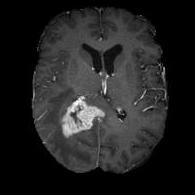

We argue that the sub-optimal paradigm of processing different abstractions within a single CNN pipeline can be remedied through the effective processing of information in a structured manner. Consequently, we devise strategies for disentangling the edge and texture information within a single training pipeline. Figure 2 illustrates how our proposed module, dubbed EG-CNN, can be paired with any existing CNN encoder-decoder to improve segmentation quality near intensity edges. We have applied our EG-CNN to the tasks of brain and liver tumor segmentation in medical images (Figure 3).

(1) Brain MR (2) Liver MR (3) Liver CT (4) Lung CT